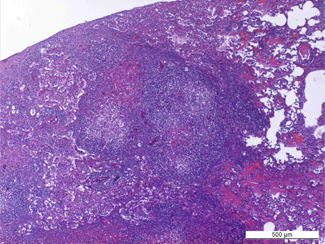

Patrons moleculars de Legionella

Les torres de refrigeració estan implicades en la majoria de brots comunitaris de legionel·losi. En aquest treball es va estudiar la variabilitat genotípica dels patrons moleculars de Legionella pneumophila en 34 torres de refrigeració. La gran diversitat genotípica de...